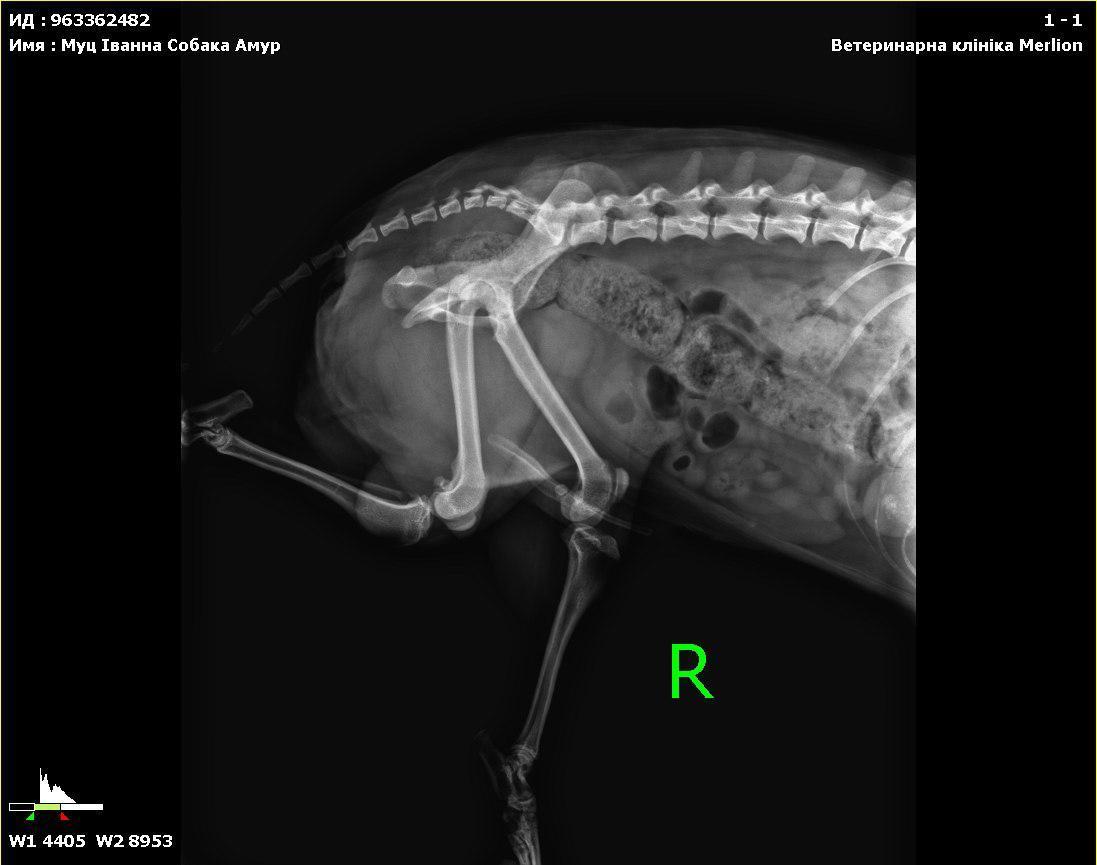

In der Klinik stellte sich heraus, dass Gucio etwa 3 Jahre alt ist und eine gebrochene Beckenregion hat. Wahrscheinlich wurde er von einem Auto angefahren. Deshalb konnte er sich nicht bewegen und lag an einer stark befahrenen Straße — ohne jede Chance, wenn niemand angehalten hätte.

Er erhielt erste tierärztliche Hilfe — Untersuchung, Impfung, Entwurmung. Sein Zustand wurde als schwer eingestuft: starke Unterkühlung, Erschöpfung und eine Verletzung, die eine langfristige Behandlung und Rehabilitation erfordert.